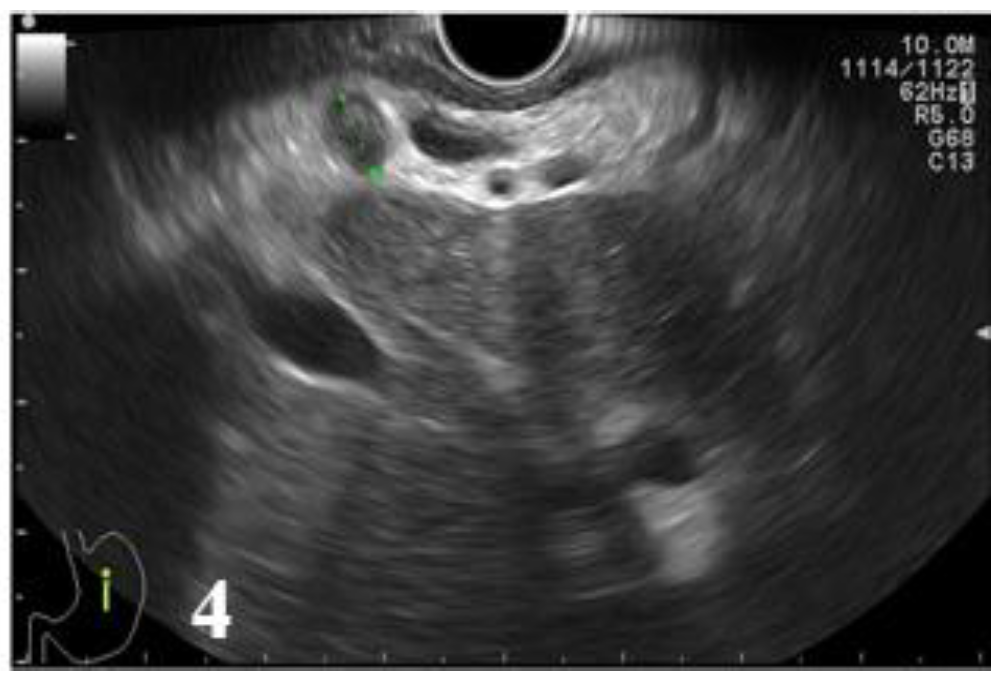

Therefore, of 19 cases of histologically diagnosed tumors as T3, 7 cases were incorrectly diagnosed: 4 cases were under-staged as T2 (21.05%) and 3 cases over-staged as T4 (15.79%). In case of T4 tumors, endoscopic ultrasound correctly diagnosed 3 cases, while in 3 cases endoscopic ultrasound erroneously considered T3 tumors as T4. A T4 tumor case was under-staged (25%) (Figure 3 and Figure 4, Table 10).

Figure 4.

EUS image showing a round lymph node with preserved hilum, with a diameter under 10 mm, located in the hepatic hilum.